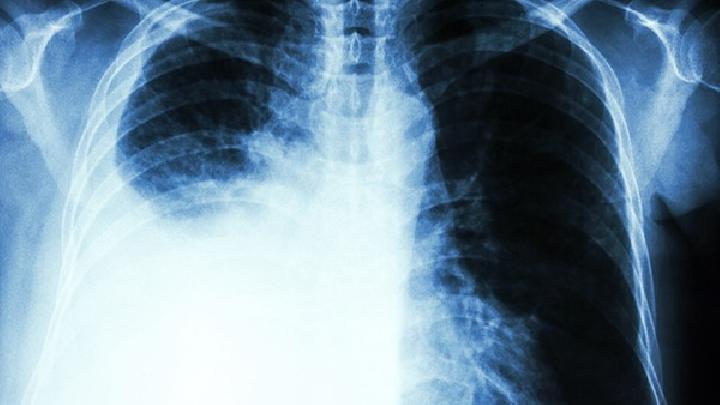

Wegener肉芽肿各年龄均可发病,但以中年男性多见,肺部病变可轻可重,严重者可以致命,2/3病人可出现胸部X线异常,可单侧受累,也可双侧受累,主要表现肺部浸润影或结节,有的伴空洞形成,由于支气管病变可引起肺不张,也可出现胸膜增厚及胸腔积液,病理活检往往表现为肺组织坏死,伴肉芽肿炎症,浸润细胞包括中性粒细胞,淋巴细胞,浆细胞,嗜酸细胞以及组织细胞,血管炎症可导致血管阻塞及梗死;1/3患者可出现肺毛细血管炎出现咯血症状,此外,有些患者还可出现肺间质纤维化,急慢性细支气管炎,闭塞性细支气管炎等等。